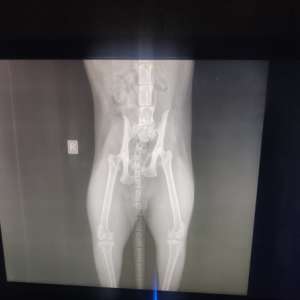

В ночь с 08 на 09 ноября собаки зверски истерзали кота. Мы сразу же поехали в ветеринарную клинику ("Зоосити Лайф", просп. Победы, 18Б), там поставили диагноз перелом позвоночника и перелом тазобедренного сустава.

❗Нужно делать срочную операцию на позвоночник (с установкой транспедикулярных винтов), такую операцию делают всего в трех клиниках Казани, также нужна операция по восстановлению тазобедренного сустава и ампутация хвоста. У кота полностью не двигается задняя часть туловища.